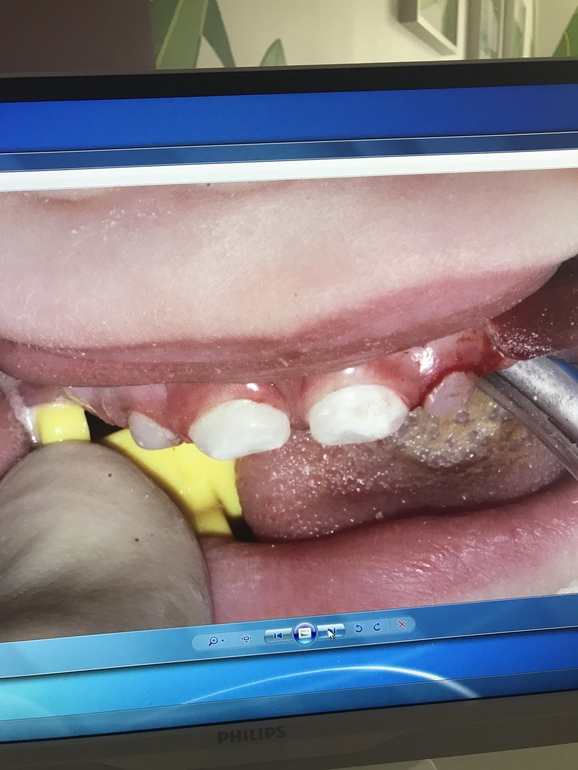

Вчера вылечили и реставрировали зубы младшему. 4 зуба из 6... 2 часа под Севоран. Спасибо огромное врачам клиники Ваш Стоматолог они умнички и проделали колоссальную работу! У сына были 2 пульпита и кариес на передних верхних резцах. Обошлось лечение в 33.500₽ . Теперь ребёнок опять может без дискомфорта есть холодное/горячие / кислое / твёрдое ! наркоз перенесли хорошо , в пятницу едем на осмотр после операционный ! Для тех кому интересно приложу фото до и после

Зубки конечно ещё будут реставрироваться по необходимости